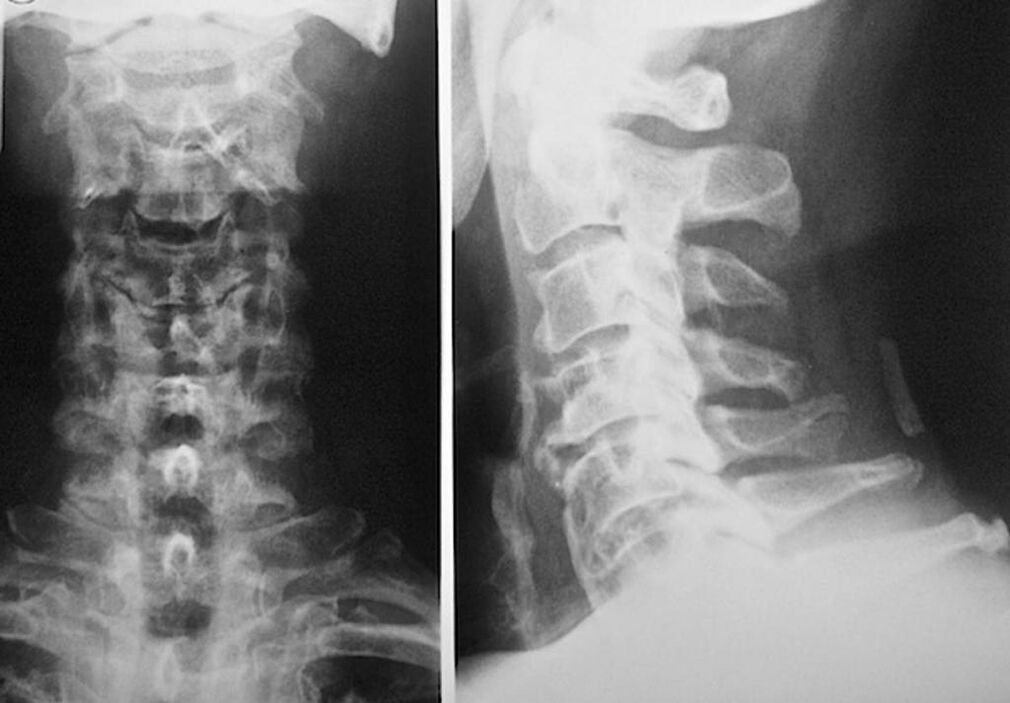

Pro diagnostiku a přesné posouzení stavu meziobratlových plotének se používají následující metody výzkumu:

- Radiografie.

- CT vyšetření.

- Magnetická tomografie.

- Ultrazvukové skenování krčních cév.

Každá z nich je zcela zdravotně nezávadná a nepředstavuje žádnou hrozbu nadměrné expozice. Diagnózu osteochondrózy krčních obratlů, jejíž léčba bude prováděna po celý zbytek života, lze provést po jednoduchém vizuálním vyšetření. To snadno zvládne každý ortoped. Výjimkou je první stadium onemocnění, kdy nejsou zaznamenány žádné viditelné patologie cervikální oblasti.